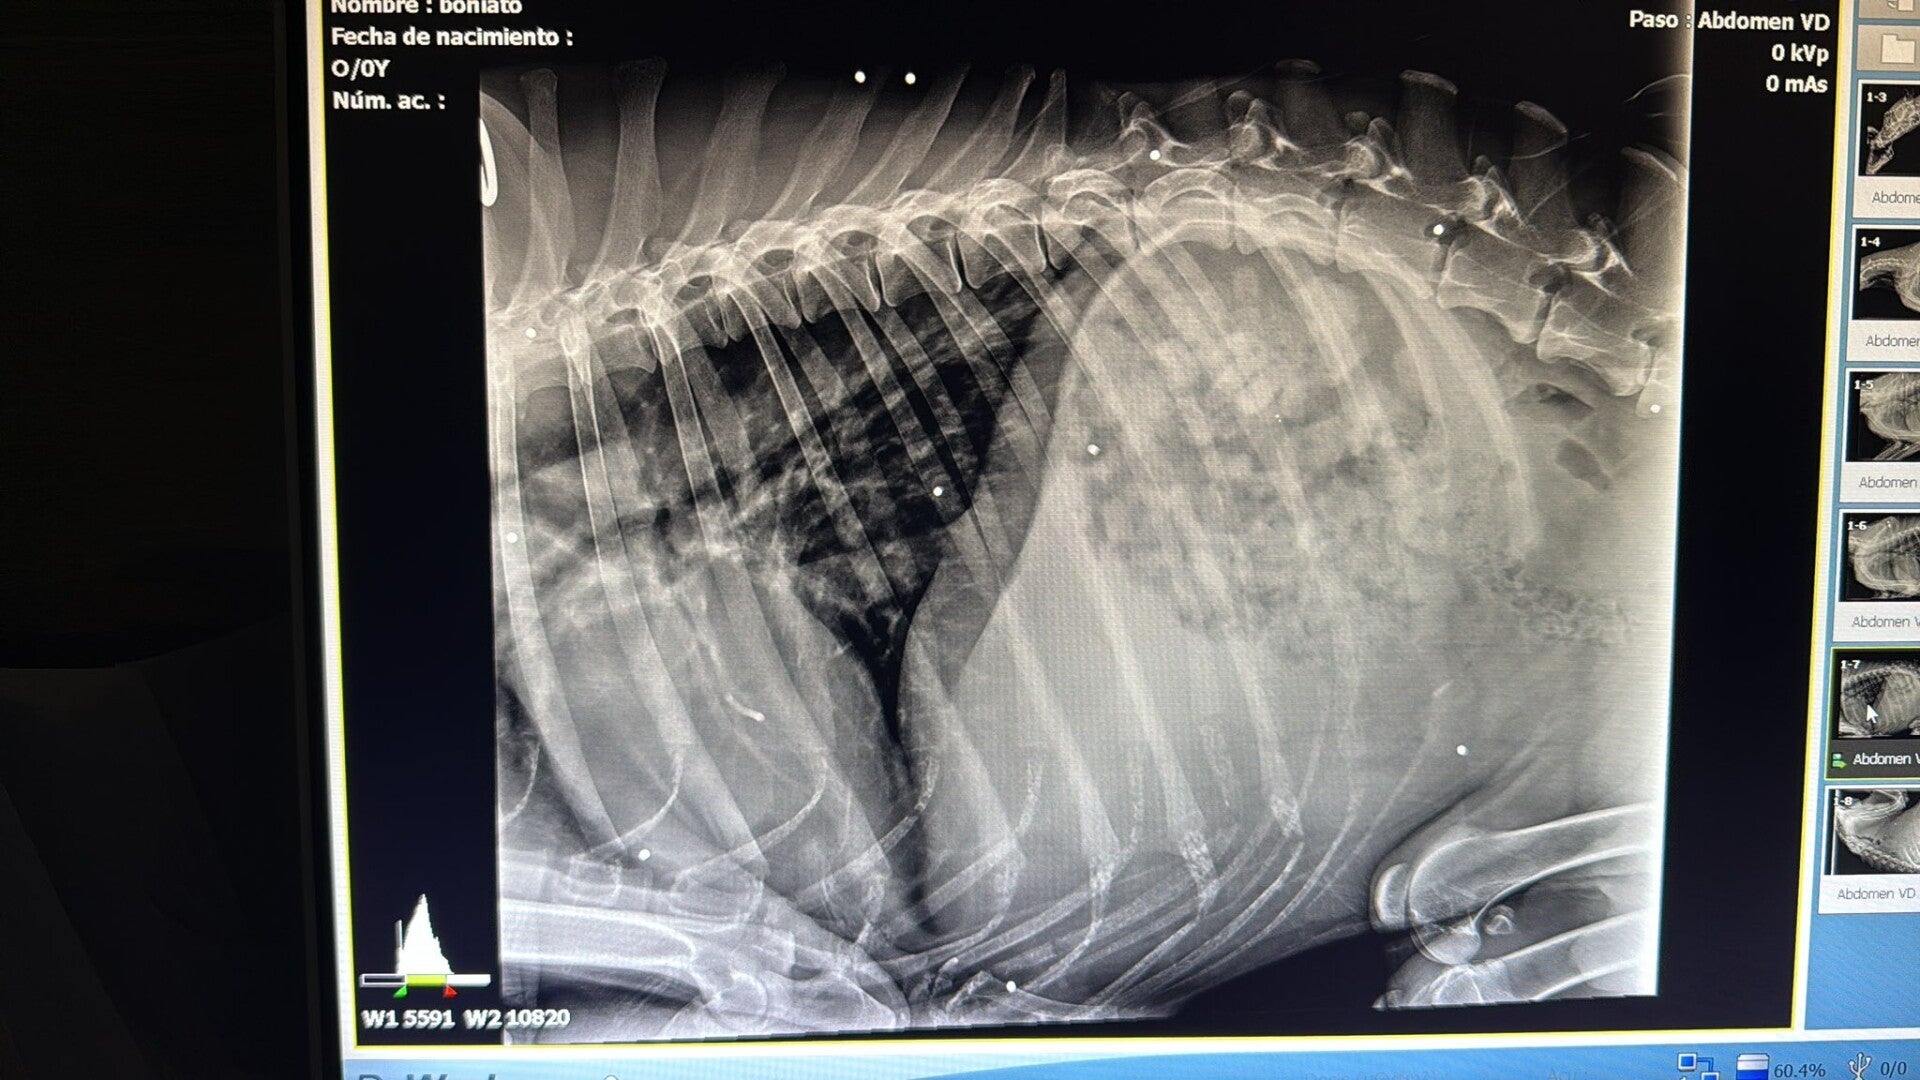

Dit zijn de röntgenfoto’s van het kleine lijfje van Boniato. Elk wit puntje dat je ziet is een stukje lood. Ze zijn zelfs gestopt met tellen hoeveel het er zijn. Er zit lood in bijna elk deel van zijn lichaam, zelfs bij zijn hart, longen en langs zijn wervelkolom. Iemand heeft simpelweg geprobeerd hem te doden door herhaaldelijk op hem te schieten — een triest en herkenbaar stempel van een jager. Geen woorden voor…